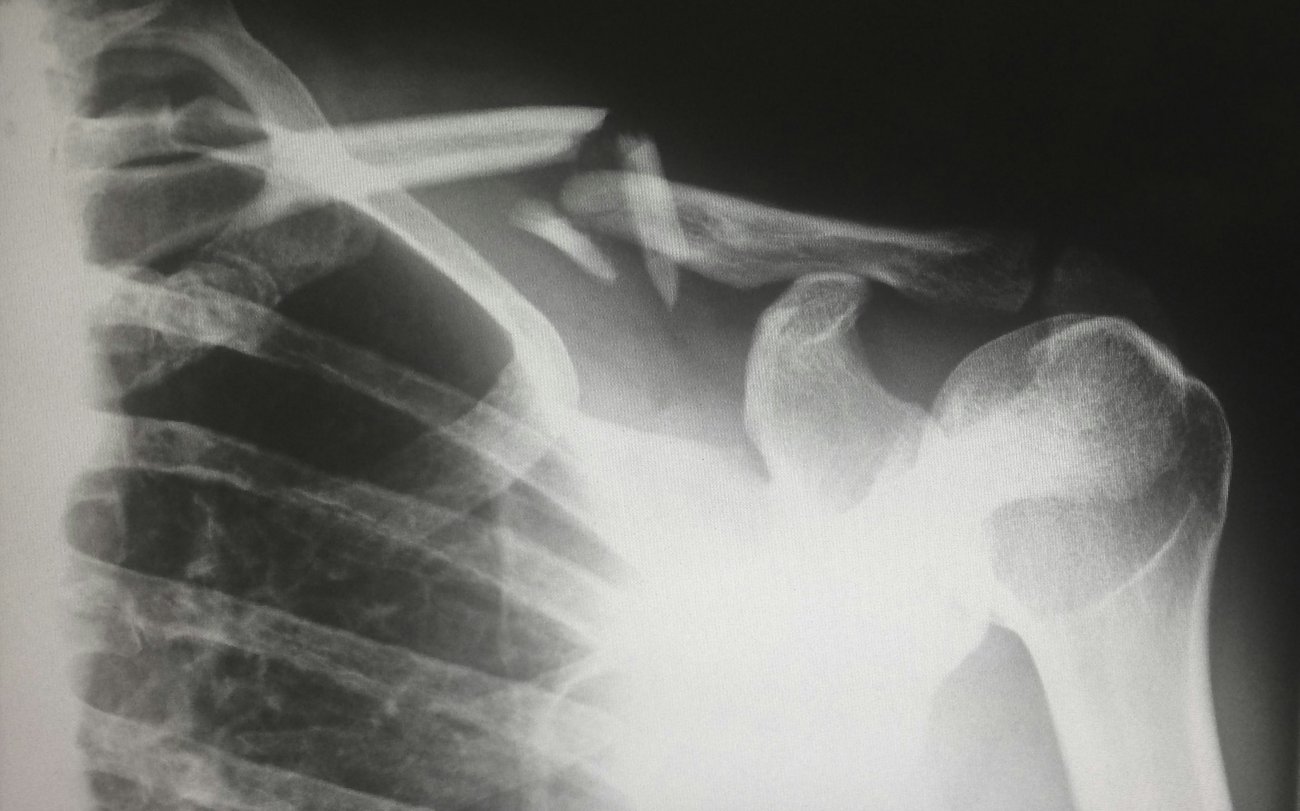

The vast majority of clavicle fractures occur in the midshaft. For surgical treatment, two fixation methods dominate: the intramedullary nail fixation and the plate fixation. The optimal treatment is still widely debated, particularly when it comes to wound complications. This systematic review and meta-analysis aimed to compare the existing evidence on the two methods.

11 studies with a total of 749 patients were included in this study, comparing wound infection, surgical incision length, operative time, dehiscence, blood loss, and length of stay.

The pooled analysis found significantly lower odds of wound infection in the intramedullary nail fixation group compared to the plate fixation group (p<0.0001).

The pooled analysis found intramedullary nailing to result in a shorter wound length, shorter operation time, less intraoperative blood loss, and a shorter length of stay compared to plate fixation (p<0.05 for all).

The pooled incidence of dehiscence was not significantly different between groups.

Bottom line. Intramedullary nailing could provide significant advantages over plate fixation for the treatment of midshaft clavicle fractures, reducing infection risk and improving peri-operative parameters.